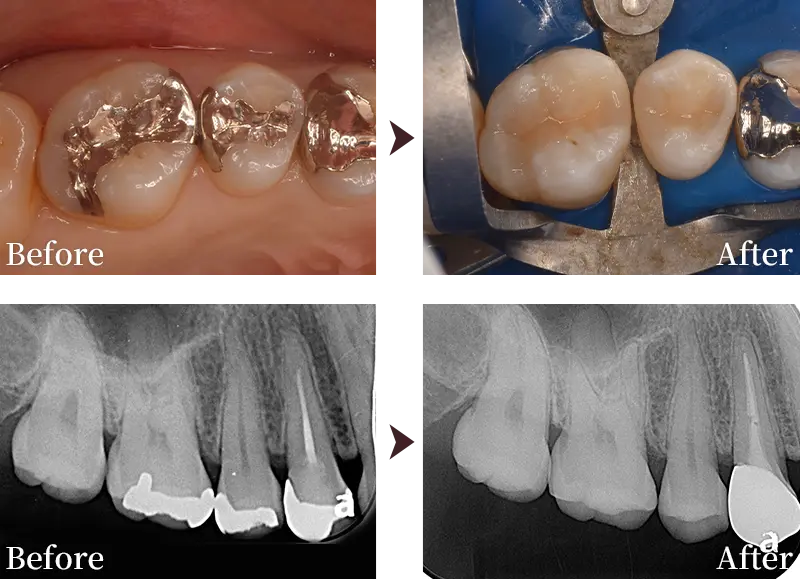

症例紹介1

症例2

主訴 虫歯を治したい

治療内容 右上6番のダイレクトボンディング

治療回数 1回

標準費用(自費) 6万円(税込)

リスク・副作用

• 経年劣化により変色や破損する場合があります。

• 治療後、歯がしみたり違和感が出る可能性があります。